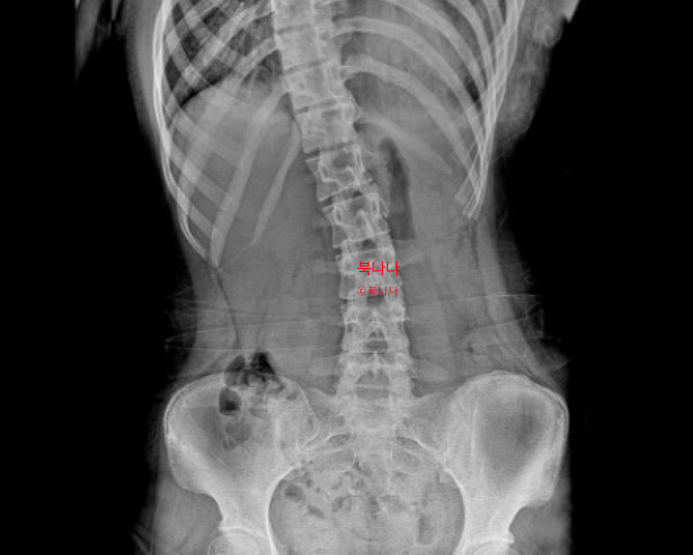

내가 반 년 동안 허리 디스크 치료하면서 효과 본 방법 3가지(물리치료, 온열기, 스트레칭)

안녕하세요, 북나나입니다. 오늘은 제가 반년 째 허리 디스크 보존 치료를 하면서 정말 효과를 많이 봤던 ...